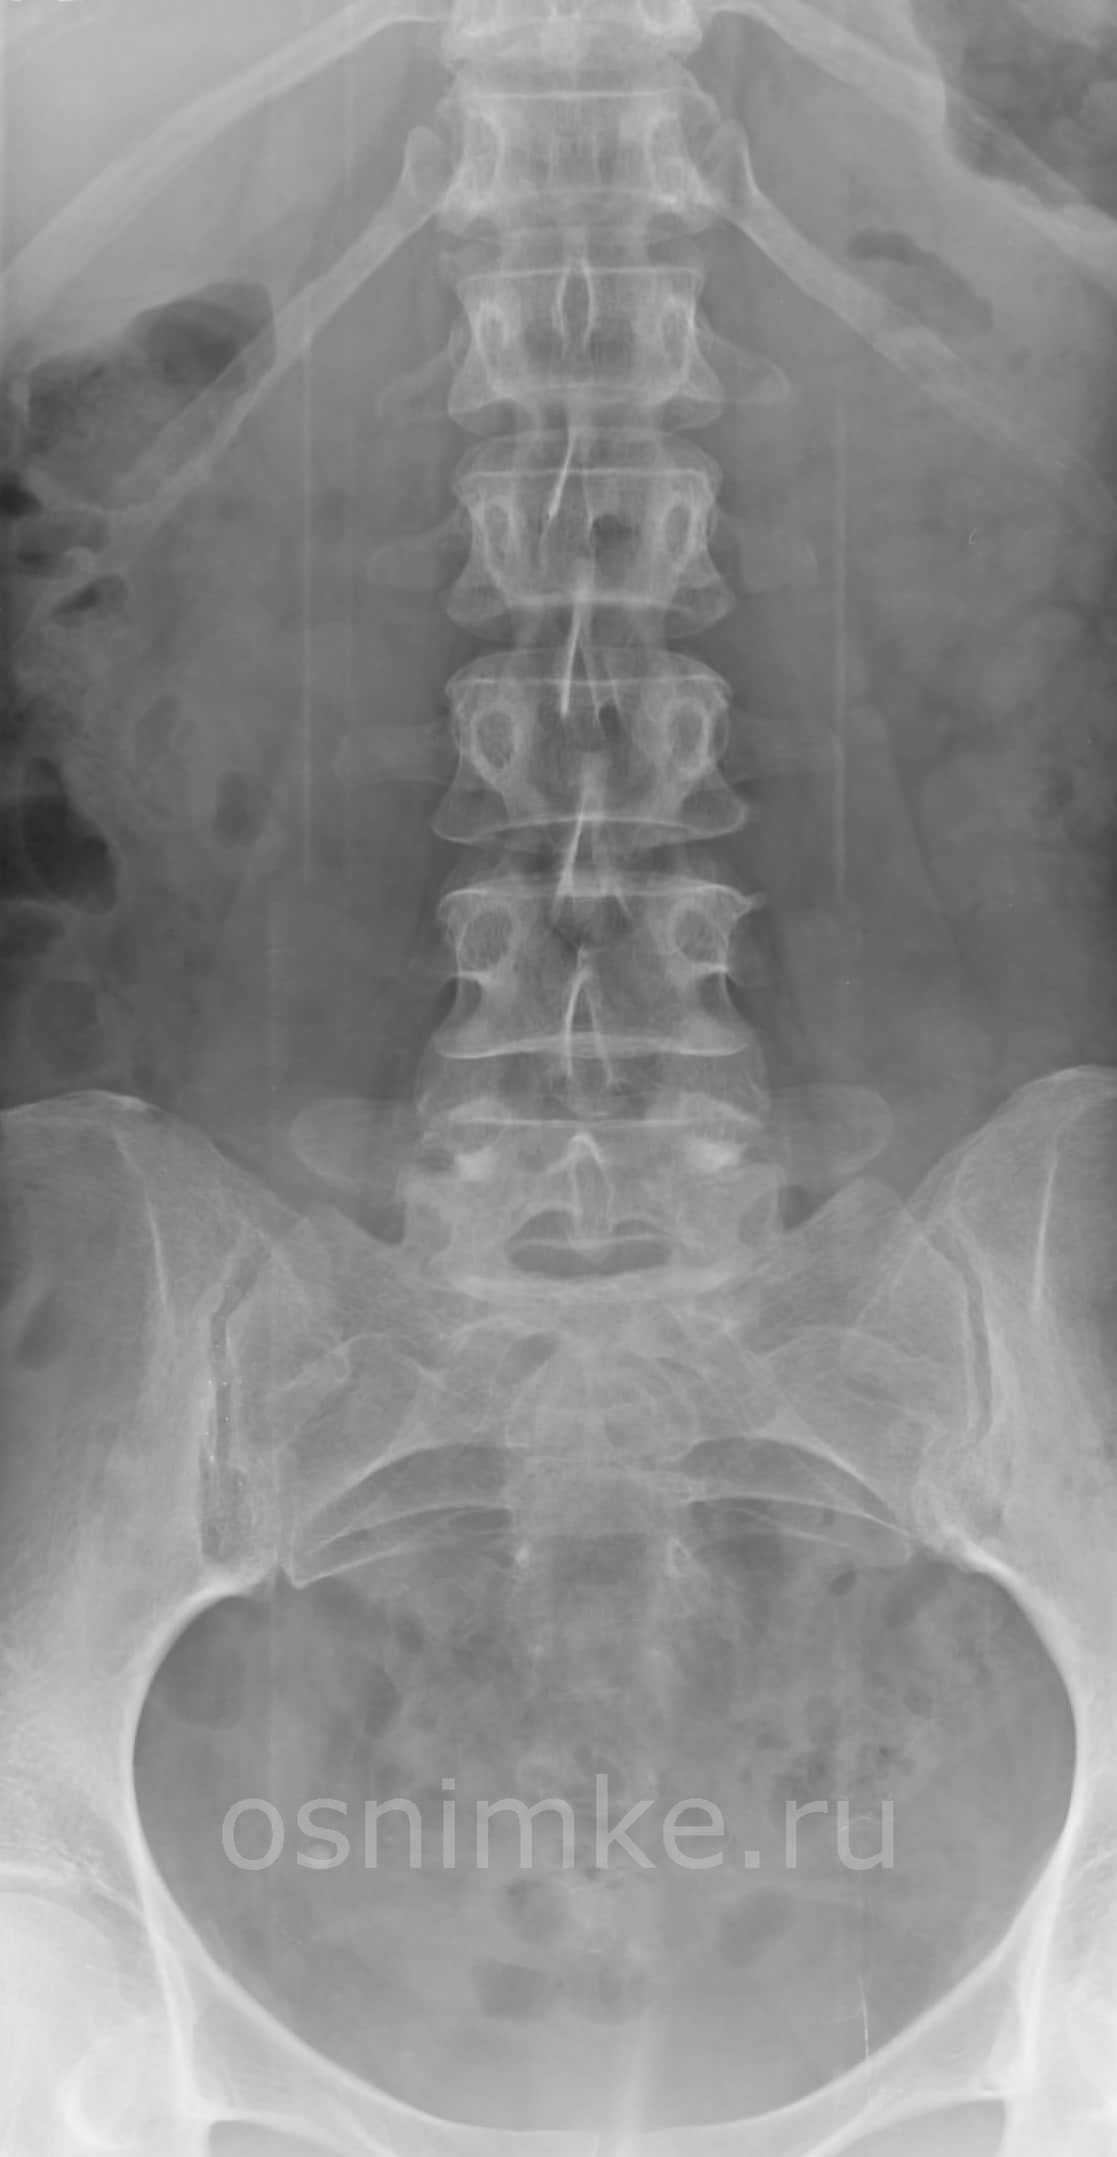

- Чаще всего вторичные отсевы рака возникают в обильно питаемых кровью губчатых костях — позвонках, причём преимущественно в испытывающих высокую нагрузку поясничных и грудных отделах позвоночника.

- Далее по частоте следуют метастазы в костях таза — почти половина всех случаев, типичные локализации — подвздошная и лонные кости.